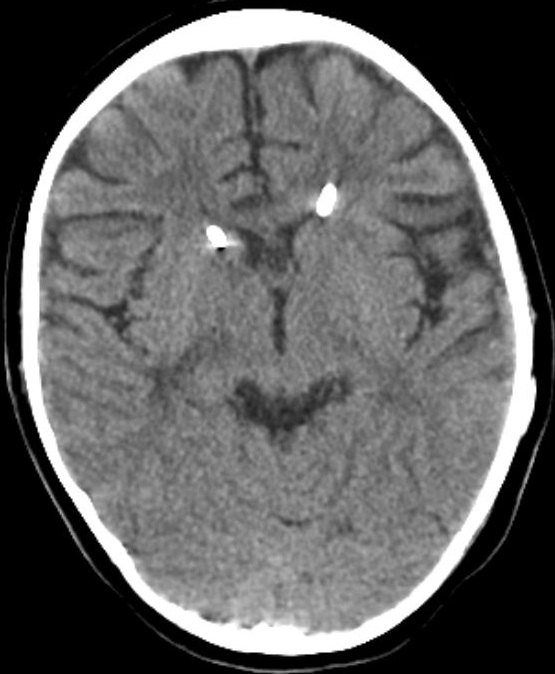

Figure 4: one year follow up CT scan showing the Cather sin place and the normal ventricular system